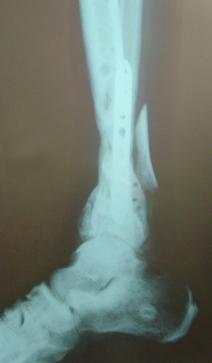

Pre-corrective surgery X-Rays of the damaged right & left legs / ankles

These x-rays were taken at Dr Armendariz’s office, just prior to performing any corrective surgery. As can be seen in these images,

there was no tibia bracing provided by Dr. Keller. Liam was released from Dr Keller’s care with instructions that full weight bearing could

be accomplished within 2 months of Keller’s last surgical procedure. The best example to examine is the second image (from the left) of the

top how. Notice how the bones that should be aligned with the tibia are in fact on the other side of the leg. The third image shows how badly

Liam’s left foot was twisted as a result of the pool placement of the external fixation. What is not obvious is that the screw at the bottom

of the plate on the right fibula missed being screwed into the plate.